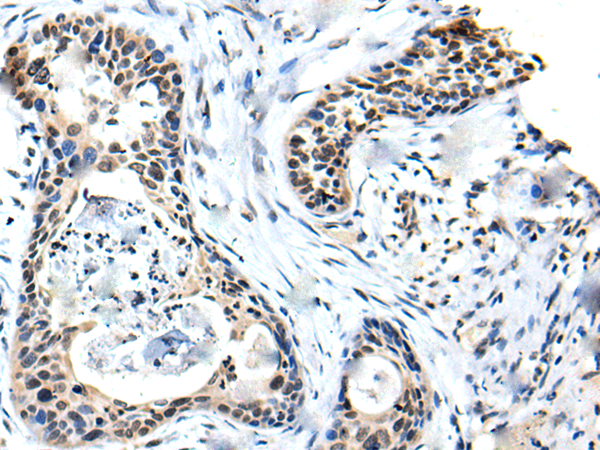

ELISA, IHC |

IHC positive control: |

Human cervical cancer |

IHC Recommend dilution: |

20-100 |